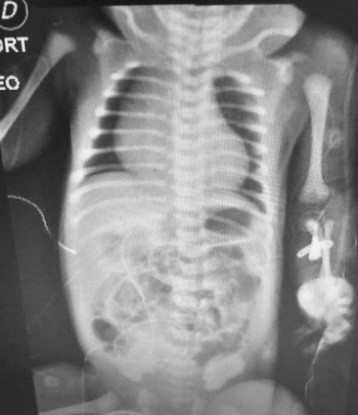

Figura 1: Radiografía de tórax

Radiografía de tórax al mes de nacimiento realizada en neonatología.

Paciente masculino de 4 años, peso real 20 kg, con diagnóstico prenatal de enfermedad de Ebstein severa, con score Great Ormond Street Echo (GOSE) grado 3, cardiomegalia y cianosis, ingresó a sala general para cursar internación preoperatoria de cirugía cardiovascular programada. A continuación se presenta la placa radiográfica al mes de nacimiento, cursando internación en sala de neonatología (Figura 1). Mes previo a la intervención quirúrgica se realizó un ecodoppler cardíaco, que informó: Displasia severa de la válvula tricúspide, valvas engrosadas, con inserción distal marcada de la valva septal con adherencia de la misma al septum interventricular, ventrículo derecho (VD) anatómico 45 mm, VD funcional 18 mm (38 %), índice de GOSE 1.2 (Grado 3), comunicación inter-auricular (CIA) amplia (16 mm), con cortocircuito bidireccional a predominio derecha-izquierda. Al siguiente día del ingreso, se realizó la cirugía de Glenn y resección parcial de lonja auricular derecha con clampeo, la cirugía duró 7 horas, el tiempo de circulación extracorpórea (CEC) fue 70 minutos, ingresó a la unidad de terapia intensiva (UTI) intubado donde se lo vinculó a ventilación mecánica invasiva (VMI) y se entregó ONI a 20 ppm, por presentar presión arterial pulmonar mayor a 25 mmhg y saturación de pulso 50 %. El paciente presentó drenaje mediastinal, pleural y sonda vesical, cables de marcapaso transitorio auricular y ventricular. Se administró milrinona, dobutamina, y se transfundió una unidad de glóbulos rojos. Para la administración de VMI se utilizó el respirador Dräger Evita V300, en modo pediátrico. El modo ventilatorio que se utilizó fue presión control, ventilación mandatoria intermitente sincronizada (PC-SIMV), la presión soporte y presión inspiratoria configurada por el operador estuvo destinada a entregar volumen corriente de 6 ml/kg peso real del paciente. Para la entrega del ONI se utilizó el dispositivo Vaso Kinox de la empresa Air Liquide Healthcare, se comenzó con una entrega de 20 ppm. La dosis entregada se controló a través de sensor proximal al paciente conectado en la rama inspiratoria del circuito ventilatorio, visualizado a través de un monitor BedFont (Box Nox2). Se presenta a continuación la placa radiográfica del paciente una vez ingresado a unidad de cuidados críticos (Figura 2). Cursando segundo día de postoperatorio (POP) el paciente permaneció sin sedación, respirando en modo espontáneo, y con inotrópicos en descenso. Persistió la HTP evidenciada por ecocardiograma. Se realizó gasometría de control, y en acuerdo con los servicios de atención involucrados se decidió desvincularlo de la VMI, cumpliendo un total de 38 horas, posterior a la extubación se vinculó a cánula nasal de alto flujo (CNAF) (se utilizó cánula nasal Optiflow junior de Fisher & Paykel) continuando el tratamiento con ONI. Para medir precisamente las ppm entregadas se colocó un catéter nasofaríngeo (Nelaton n.º 8 cortada de 7 cm) conectada al sensor (Figura 3). Los parámetros requeridos en CNAF fueron 35 L/min y 85 % de fracción inspirada de oxígeno (FI02). Se continuó entregando la misma dosis de ONI a 20 ppm. Diariamente se registró la entrega de ONI por CNAF, teniendo en cuenta la diferencia existente entre la entrega de ppm configurada en el visor Kinox y la entregada en nasofaringe detectada por el catéter y expresada en el monitor, debido a la entrega de ONI por CNAF es un sistema abierto con presencia de fugas se observó una diferencia en la medición, la cual no ocurrió al entregarlo a través de un sistema cerrado como lo es la VMI con tubo endotraqueal (Figura 4). El ONI fue entregado mediante CNAF hasta el 4º día POP, cumpliendo 87 horas, se decidió suspender ONI con los siguientes parámetros clínicos, 107 frecuencia cardiaca (FC), 15 frecuencia respiratoria (FR), 90 % saturación de pulso (SAT), 15 L/min – 60 % FIO2, 12,9/22 ppm. A las 3 horas de suspender el ONI se decidió reconectarlo debido a la presencia de cianosis, y desaturación, SAT 69 %, 132 FC, 25 FR, al constatar el efecto rebote, se modifican los parámetros de CNAF a 25 L/min, 70 % FIO2, y se reconectó nuevamente ONI a 12 ppm. Una hora posterior a la reconexión, se logró estabilidad clínica, y los parámetros de CNAF y ONI no fueron modificados por 24 horas, al día siguiente se descendió los parámetros de ONI y CNAF progresivamente, y al día 6° POP se suspendió la administración de ONI y CNAF, y se desescaló a cánula nasal de bajo flujo (Figura 5). Parámetros previos a la suspensión de ONI y CNAF: 120 FC, 18 FR, 82 % SAT. CNAF: 15 L/min, 60 % FI02. ONI: 0,8 ppm (4 ppm configurado), 60-52 % FIO2. Cumpliendo 126 horas de ONI total y 91 horas de CNAF. Al día 15º POP se retiró el aporte de oxigenoterapia, y al día 18º, se realizó ecocardiograma que informó Glenn normofuncionante y CIA amplia con cortocircuito bidireccional. El paciente fue externado. A continuación, se presenta una tabla que refleja las horas brindadas por cada terapéutica en relación a la entrega de ONI (Tabla 1). Todos los datos brindados fueron recabados de las planillas diarias del servicio de kinesiología, y evoluciones diarias del servicio de cirugía cardiovascular, diagnóstico por imágenes y médicos de UTI.